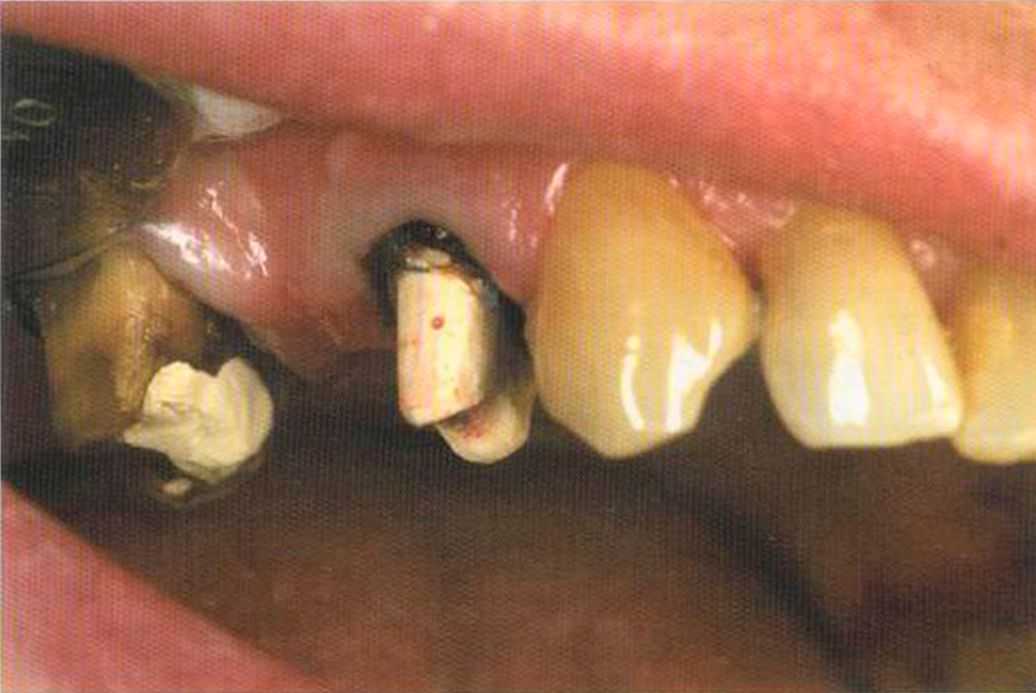

Безметалловые реставрации также отлично подходят для пациеьипов с непереносимостью всех металлов. У этого пациента положительная аллергологическая проба даже на сплавы с высоким содержанием золота.

Так как 21 зуб депульпирован, и культя не подходит для изготовления коронки, была изготовлена культевая вкладка из Zirconia. Эта методика очень дорогая, но в данном случае были все показания для ее применения.

Го то вый результат. Зуб 21 со штифтом из Zirconia. От 12 до 21 изготовлены три отдел1>ные коронки 1п-Сегат. Все зафиксировано в полости рта на цемент Panavia ТС.

На примере большой работы я подробно объясню этапы изготовления индивидуальных штифтов из Zirconia.

Первые сложности возникают уже при препарировании. Корневые каналы должны быть расширены максимально, в противном случае изготовление штифтов невозможно. При этом стенки корней не должны быть слишком тонкими, иначе они могут поломаться при цементировании или в последующем при жевательных нагрузках.